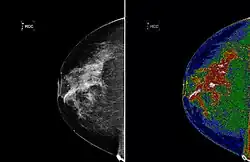

A region of interest (often abbreviated ROI) is a sample within a data set identified for a particular purpose.[1] The concept of a ROI is commonly used in many application areas. For example, in medical imaging, the boundaries of a tumor may be defined on an image or in a volume, for the purpose of measuring its size. The endocardial border may be defined on an image, perhaps during different phases of the cardiac cycle, for example, end-systole and end-diastole, for the purpose of assessing cardiac function. In geographical information systems (GIS), a ROI can be taken literally as a polygonal selection from a 2D map. In computer vision and optical character recognition, the ROI defines the borders of an object under consideration. In many applications, symbolic (textual) labels are added to a ROI, to describe its content in a compact manner. Within a ROI may lie individual points of interest (POIs).

Medical imaging standards such as DICOM provide general and application-specific mechanisms to support various use-cases.